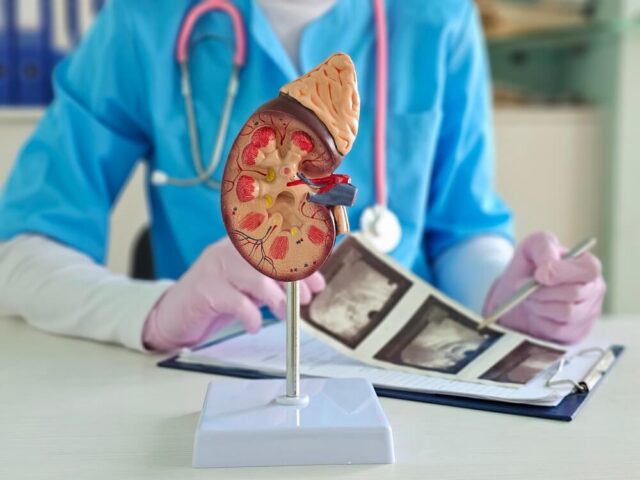

Kamen u bubregu predstavlja jedan od najčešćih uroloških problema. Istraživanja pokazuju da pogađa oko oko 10% svetske populacije. Pri čemu...

Pročitajte višeKada je potrebno uraditi ultrazvuk bubrega?

Ultrazvuk bubrega predstavlja jednu od najvažnijih dijagnostičkih metoda u savremenoj medicini, jer omogućava brz, bezbolan i pouzdan uvid u stanje...